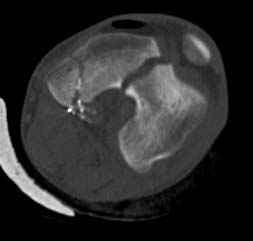

У молодого человека огнестрельное слепое ранение н/3 правого бедра. Поступил в клинику с внутрисуставным многооскольчатым Т-отразным переломом дистального отдела бедренной кости. Дополнительно на  СТ-исследовании обнаружен перелом внутреннего мыщелка Hoffa со смещением.<br><br>

Больной взят в операционную на второй день, где из небольшого медиального доступа выполнена артротомия коленного сустава. Произведена репозиция отломков, фиксация винтами. Попутно удалена пуля. Первым делом была достигнута репозиция медиального мыщелка (перелома Hoffa, где коронарная плоскость перелома трудно поддается закрытой репозиции и фиксации. ) Затем была достигнута идеальная репозиция суставной поверхности бедра и фиксация компрессирующими headless  screws.<br><br>

Дистальный отдел бедра был дополнительно фиксирован buttress пластиной с медиальной стороны из того же разреза. Для усиления фиксации латеральной колонны -  с латеральной стороны закрытым способом из минидоступа установлена еще buttress plate.  Пулевой канал дополнительно не подвергался хирургической обработке.<br><br>